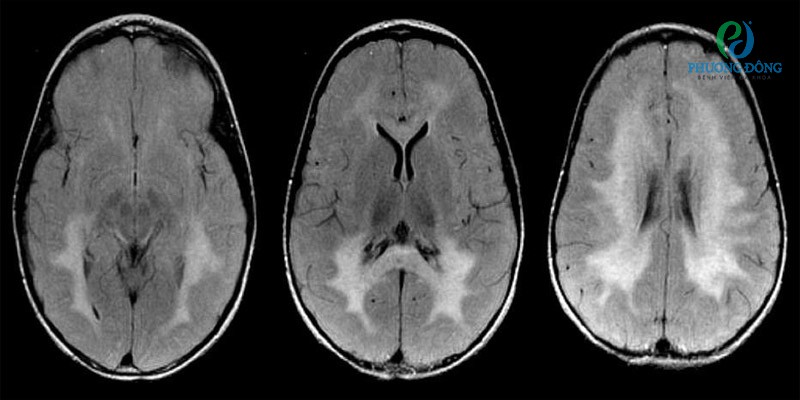

Hình ảnh cộng hưởng từ (MRI) mặt cắt ngang FlairHình ảnh cộng hưởng từ (MRI) mặt cắt ngang Flair

Ghi chú:

• Lưu ý các tổn thương chất trắng lan rộng hai bên, nổi bật hơn ở vùng phía sau.

• Chẩn đoán: Một bé gái 3 tuổi có các triệu chứng co cứng cơ tiến triển, suy giảm thị lực và chậm phát triển vận động.